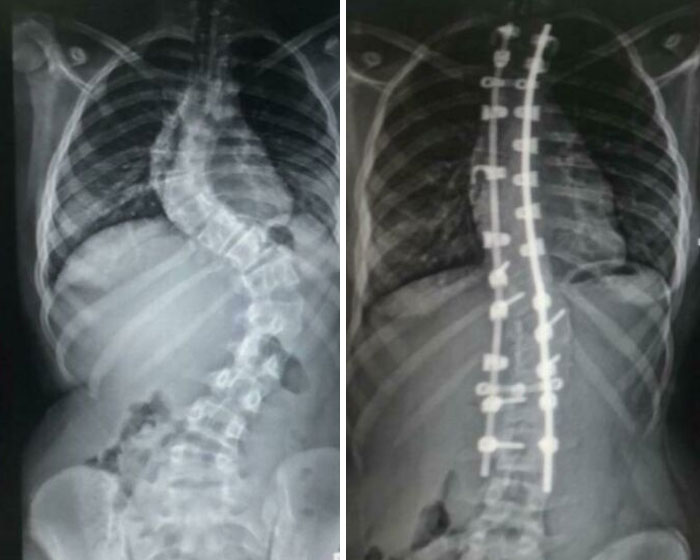

#12 Mi columna antes y después de la fusión espinal

© Foto: Usuario